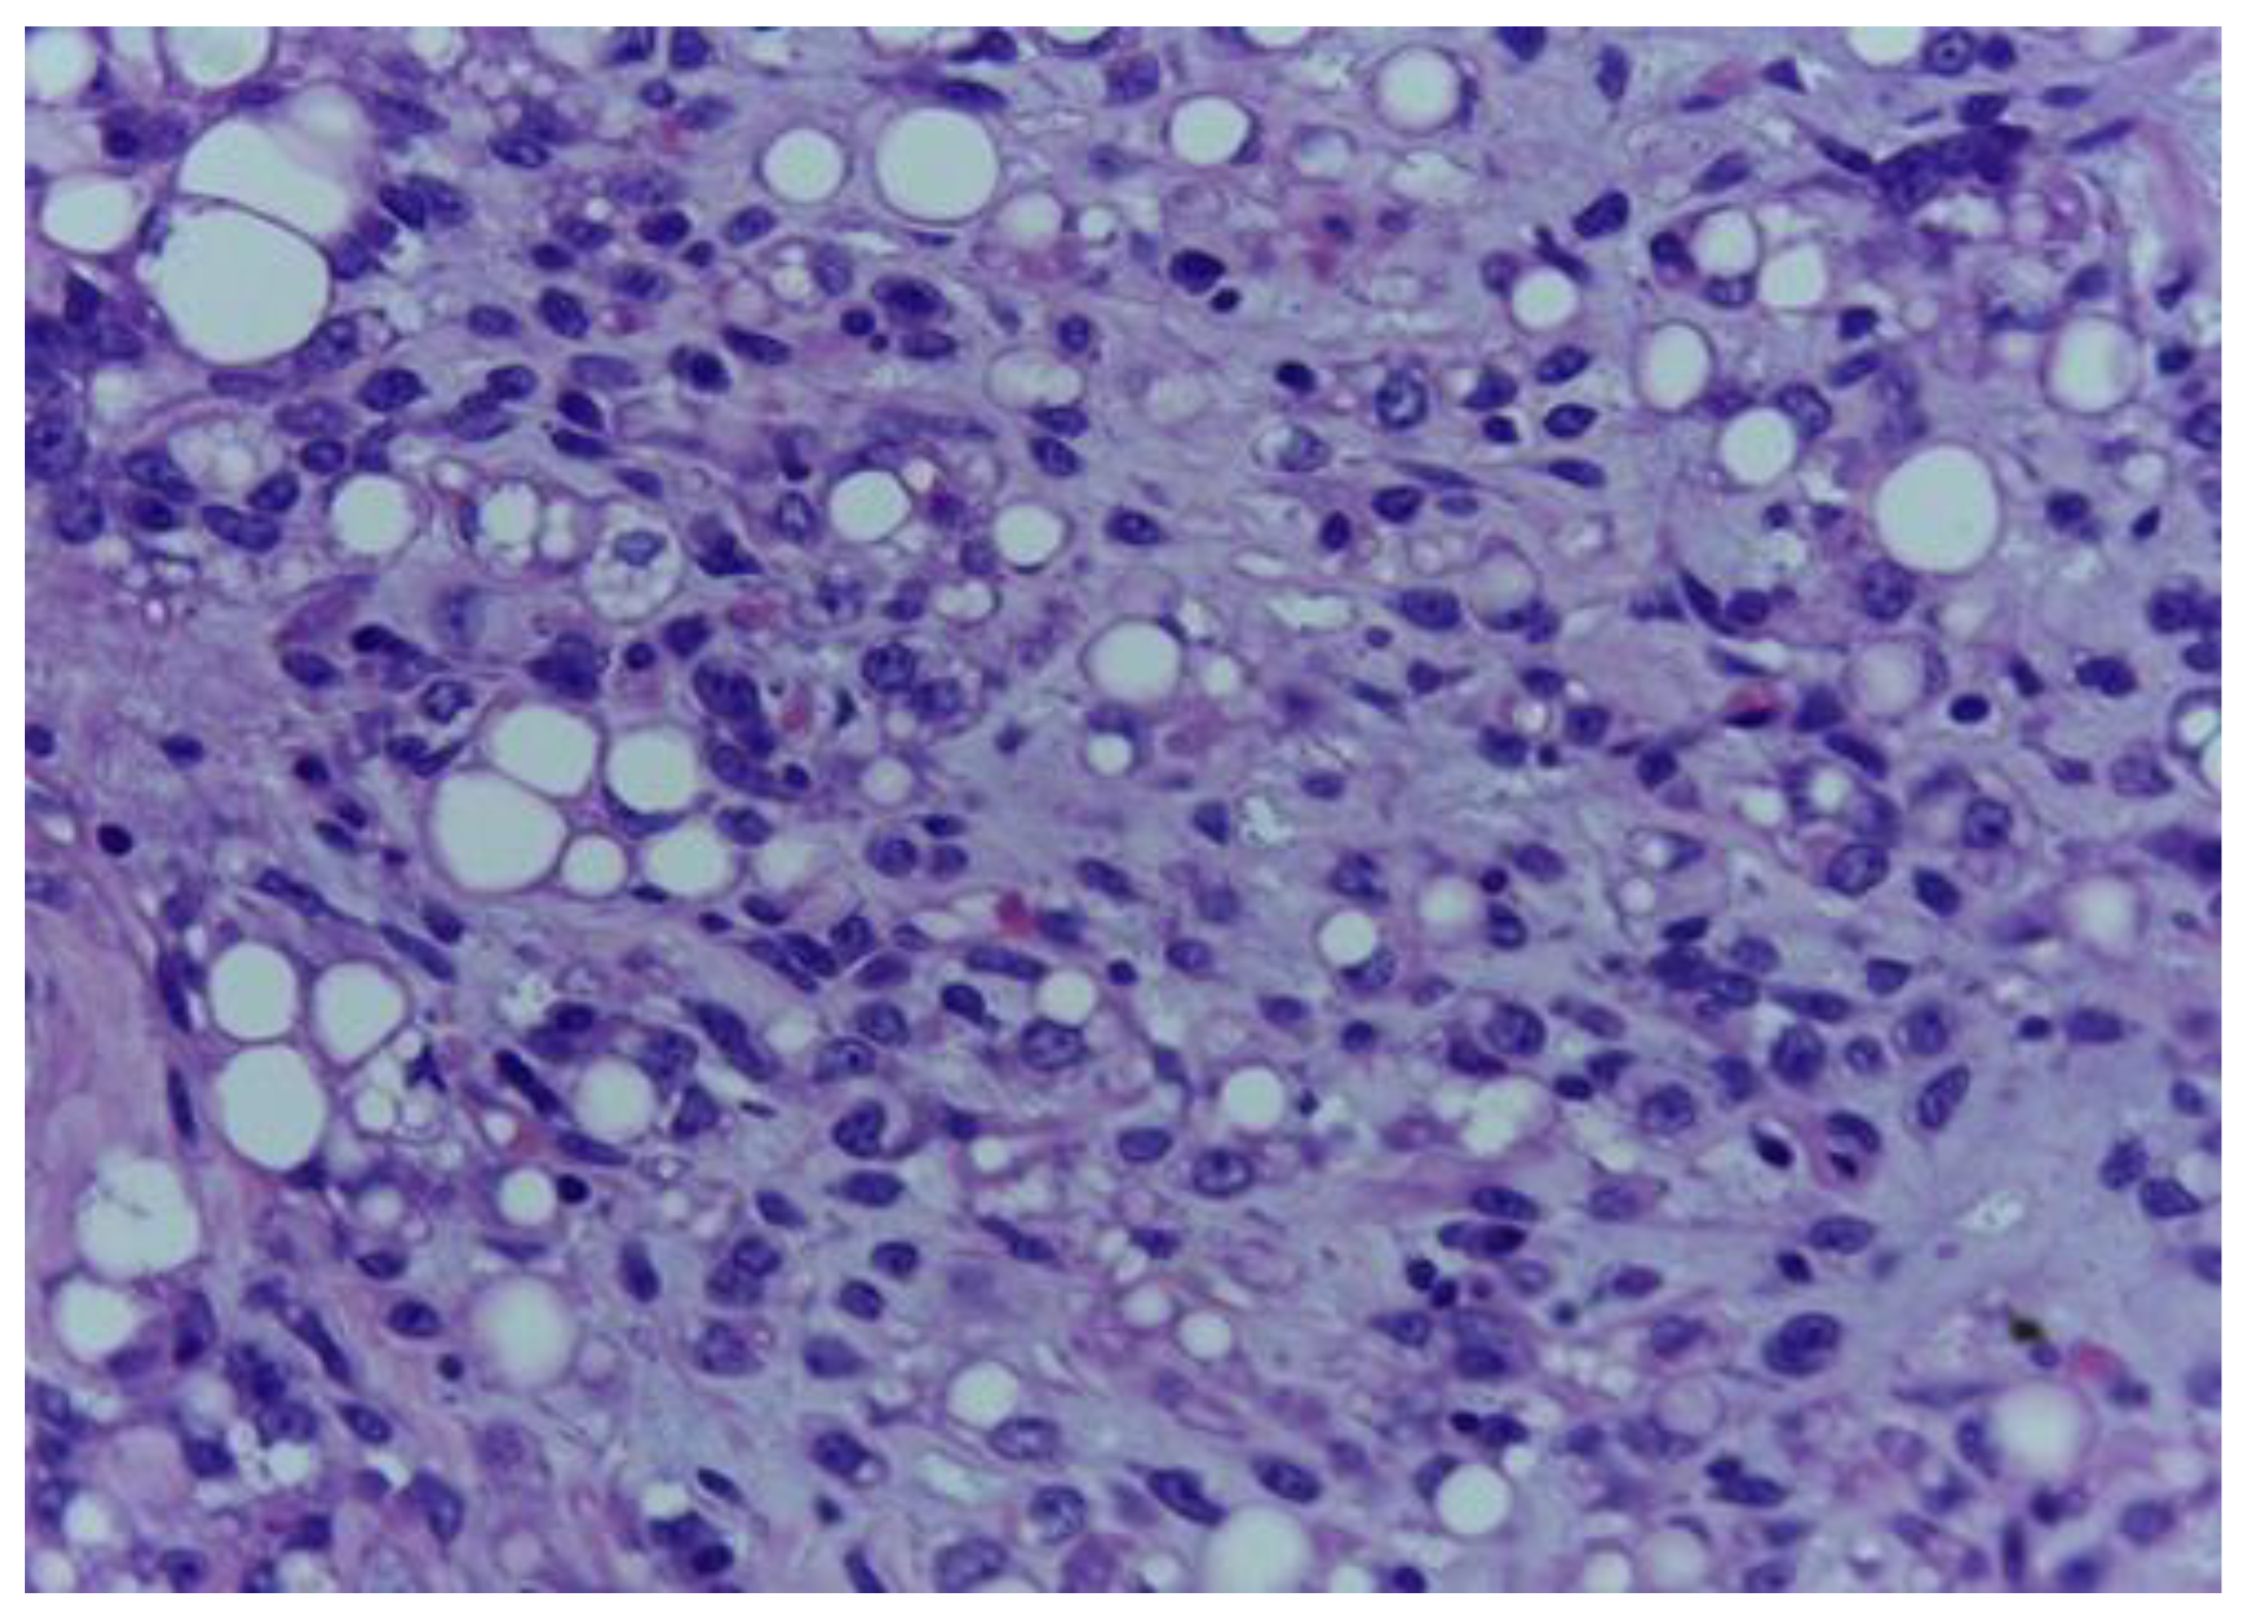

The histological examination showed a malignant mesenchymal proliferation with a lobular growth pattern, exhibiting round–oval and fusiform neoplastic cells with hyperchromatic nuclei and occasional nuclear pseudoinclusions, separated by a loose, lightly basophilic stroma, containing extracellular mucoid pools (Figure 1 and Figure 2).

Figure 2.

The tumour proliferation with adipocytic differentiation displays round and spindle neoplastic cells with hyperchromatic nuclei. H.E., ob. 400×.